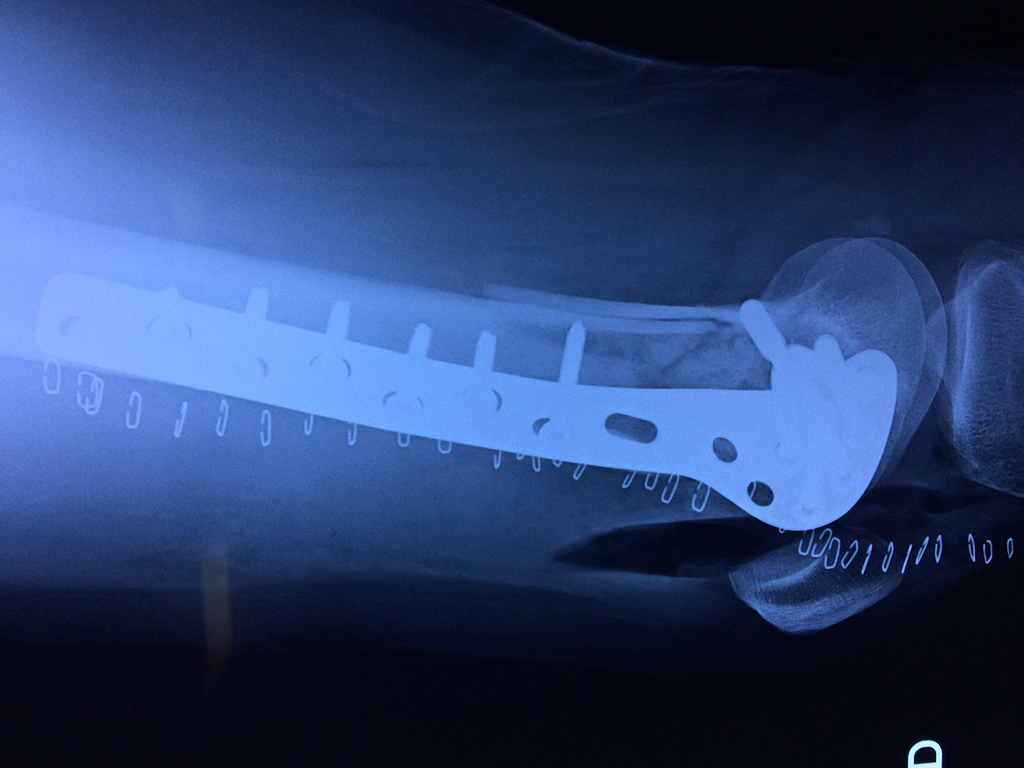

Cirugía de Rodillas

El fémur es el hueso del muslo, el segundo segmento del miembro inferior. Es el hueso más largo, fuerte y voluminoso del cuerpo humano.